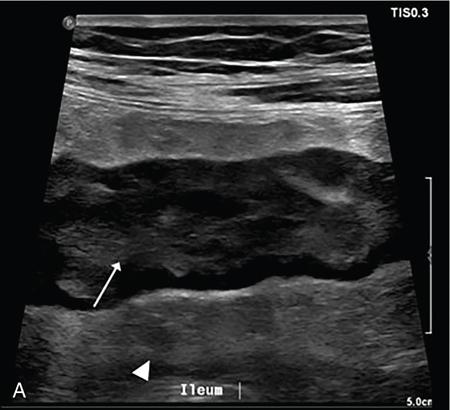

Kavita Saggar, Archana Ahluwalia, Devinder Pal Singh Dhanota, Geetika Khanna, Chander Gupta Inflammatory bowel disease (IBD) represents chronic idiopathic inflammation of the gastrointestinal [GI] tract. The common subtypes are Crohn’s disease, ulcerative colitis (UC) and indeterminate colitis (Fig. 7.11.1). Approximately 20%–25% of patients present in childhood or adolescence. Of these, nearly two-thirds of cases are caused by Crohn’s disease with an incidence of 4.56 per 1000,000 children (Fig. 7.11.2). IBD can affect any portion of the GI tract; however, children have a much higher incidence of small bowel and colonic involvement (Table 7.11.1). Currently, there is no single diagnostic test for the evaluation of IBD. Diagnosis is based on a combination of history, physical examination, serum inflammatory markers, endoscopy, histopathology and imaging. A host of imaging modalities is available for the evaluation of IBD in children. Traditionally, barium fluoroscopic studies, namely small bowel follow-through or small bowel enteroclysis (SBE) were used. However, barium studies depict only the mucosal abnormalities and do not evaluate the extraluminal extent of disease. Ultrasonography (US) is increasingly being used in the workup of patients with IBD. Small intestine contrast ultrasound (SICUS) and contrast-enhanced ultrasound (CEUS) are used for evaluation of IBD. CEUS requires intravenous administration of microbubble contrast such as Sonovue, and SICUS requires small bowel adequate luminal distension with ingestion of an iso-osmolar contrast agent such as polyethylene glycol. A recent meta-analysis of 33 studies showed that CEUS had better accuracy than US, CT and MR for the detection of inflammation and differentiation of fibrotic and inflammatory strictures. However, the extent of the disease was better evaluated by CT and MR. Currently, computed tomography enterography (CTE) and magnetic resonance enterography (MRE) have emerged as the most effective tools for imaging small bowel in patients with IBD. CTE and MRE can accurately depict the spectrum of imaging findings related to severity, extent and complications of IBD and thereby help in guiding management and assess the response to treatment. MRE is an attractive imaging modality due to lack of ionizing radiation, inherent multiplanar capability and excellent soft tissue contrast resolution. In addition, dynamic/cine imaging allows assessment of peristalsis and accurate identification of the diseased segment. The major disadvantage of MRE is high cost, lower spatial and temporal resolution and long examination time. Crohn’s disease is a transmural granulomatous disease that can affect any part of the GI tract from the oral cavity to anus, often involving multiple discontinuous segments of bowel. Patients have a genetic predilection to develop an abnormal immunologic response to environmental factors including food and gut flora, leading to a chronic inflammatory response. Small bowel is the major site of involvement. Terminal ileum is the most common location which is involved in approximately one-third patients. The colon is affected in 50% patients. In 15%–20% cases, there may be isolated involvement of the colon without affecting the small bowel. The clinical importance of small bowel Crohn’s disease is the impact that a diffuse small bowel disease is expected to have on child’s growth and development. Thus, objective evaluation of small bowel is essential in differentiating from other enteropathies and in directing the management of patients with IBD. Two methods used for imaging small bowel with barium using fluoroscopy are standard small bowel follow through (SBFT) and SBE. Small bowel evaluation with barium has long been considered the most common, noninvasive, inexpensive and easily accessible radiological method, but it has been replaced by cross-sectional imaging. In the current scenario, the only indication of barium studies is when CTE or MRE cannot be done because of nonavailability or are not feasible. Ultrasound is being increasingly used to assess the activity of Crohn’s disease, especially in paediatric patients. Greyscale ultrasound allows morphologic assessment of bowel wall and mesentery. Normal small bowel loops are easily compressible with the transducer and the wall thickness is <2 mm. The bowel loops show regular peristalsis and are mobile. Colour Doppler shows minimal intramural or perienteric vascularity. The salient sonographic features of Crohn’s disease are: There is marked concentric or eccentric bowel wall thickening [>2.5–3 mm]. The mural echogenicity depends upon the degree of inflammation and fibrosis. In the acute phase, mural stratification is maintained (Fig. 7.11.3A and B). In patients with long-standing disease, a target or pseudo-kidney appearance may be seen. In long-standing burnt-out disease, there is submucosal fat deposition. The actively inflamed bowel segments show increased vascularity on Doppler ultrasound (Fig. 7.11.4A and B). CEUS with microbubbles can objectively assess the disease activity. A stricture is seen as a segment of bowel wall thickening with apposition of the luminal surfaces. There is persistent luminal narrowing with variable degree of upstream dilatation and hyperperistalsis. Doppler imaging reveals hyperemia in strictures with an active inflammatory component. Fibrotic strictures do not demonstrate increased blood flow. A major advantage of ultrasound is real-time imaging which allows the evaluation of bowel peristalsis. The diseased segments of the bowel (inflamed or fibrotic) show reduced peristalsis and often appear fixed in position. Mesenteric inflammation is commonly seen in active Crohn’s disease. Sonography reveals thickening of mesentery with heterogeneous echogenicity due to oedema. Doppler ultrasound shows increased vascularity due to engorgement of vasa recta. Fibrofatty proliferation of mesentery seen in chronic disease appears as abnormally thickened echogenic fat that displaces the bowel loops. Reactive mesenteric lymph nodes (up to 1.5 cm) can be seen in the active inflammatory phase of Crohn’s disease. These appear as hypoechoic round or oval structures with preserved fatty hilum. Sinus tracts and fistula often arise from or just proximal to a strictured segment and appear as linear areas of altered hypoechogenicity extending from serosal surface of gut. There may be tethering and/or angulation of the affected bowel segment. Abscesses are discrete well-defined fluid collections with internal debris, septation or nondependent echogenic gas. Colour Doppler reveals peripheral hyperemia with absent blood flow centrally. Ultrasound may be falsely negative if an abscess contains a large amount of air and can be mistaken for an air-filled bowel loop. Both CTE and MRE identify the transmural, extramural and mesenteric manifestations of small bowel Crohn’s disease. The imaging findings can be categorized as: Asymmetric long segment (>3 cm) bowel wall thickening is a consistent feature of Crohn’s disease. The mesenteric border is usually more severely affected. It is imperative that the bowel should be distended when assessing bowel wall thickening. Thickening may be mild (3–4 mm), moderate (5–10 mm) or severe (>10 mm) (Fig. 7.11.5A and B). This is the most consistent finding in the active inflammatory stage, defined as increased signal intensity or attenuation on contrast-enhanced scans in a noncontracted segment of bowel in comparison with adjacent small bowel segments. Hyperenhancement may be stratified into bilaminar and trilaminar patterns. In the bilaminar pattern, there is hyperenhancement of only the inner wall (often referred to as mucosal hyperenhancement), and in the trilaminar pattern, there is inner and outer wall hyperenhancement, with the submucosal oedema giving a halo effect. Hyperenhancement may also be homogeneously transmural or patchy. A potential pitfall in contrast enhancement is that normal jejunal loops enhance more than ileal loops and collapsed bowel segments can show apparent hyperenhancement (Figs. 7.11.6A,B and 7.11.7A–C). These are defined as multifocal (>3) segmental areas of involvement with normal intervening gut loops. This is an important feature that differentiates Crohn’s disease from UC when colon is predominantly involved (Figs. 7.11.5A,B and 7.11.7A–C). This is identified as an increased signal of the thickened bowel wall on T2W images. The inflamed walls also show restricted diffusion. The hyperintense signal due to intramural oedema persists on T2W fat-saturated images differentiating it from intramural fat seen in long-standing burnt-out disease (Fig. 7.11.8A and B; refer Fig. 7.11.20A–D).